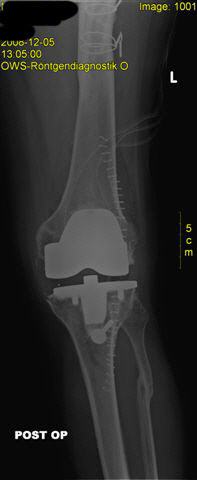

schwere X-Bein-Fehlstellung und Instabilität bei massiver Kniegelenksarthrose